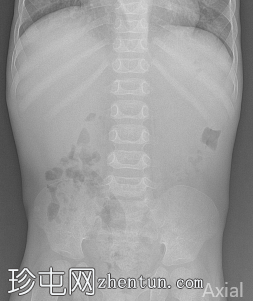

腹部平片

正位片显示舟状腹,肠道气体稀少。